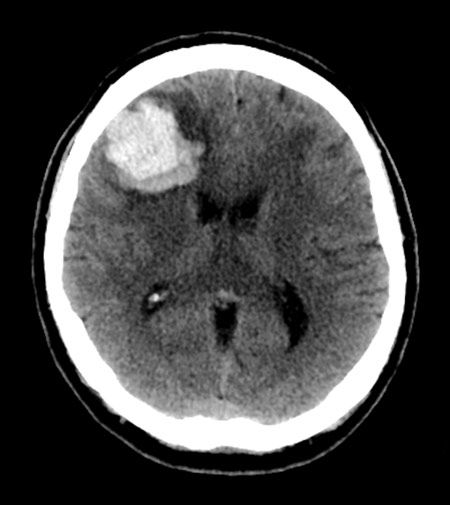

@RadMasterclass

2 days

CT BRAIN QUIZ: Non-contrast CT Brain: Sudden onset severe headache. What does the image show? A: Subdural haematoma B: Subarachnoid haemorrhage C: Intraventricular haemorrhage D: Extradural haematoma E: Intracerebral haemorrhage Start Quiz https://t.co/ATFl8YktNe